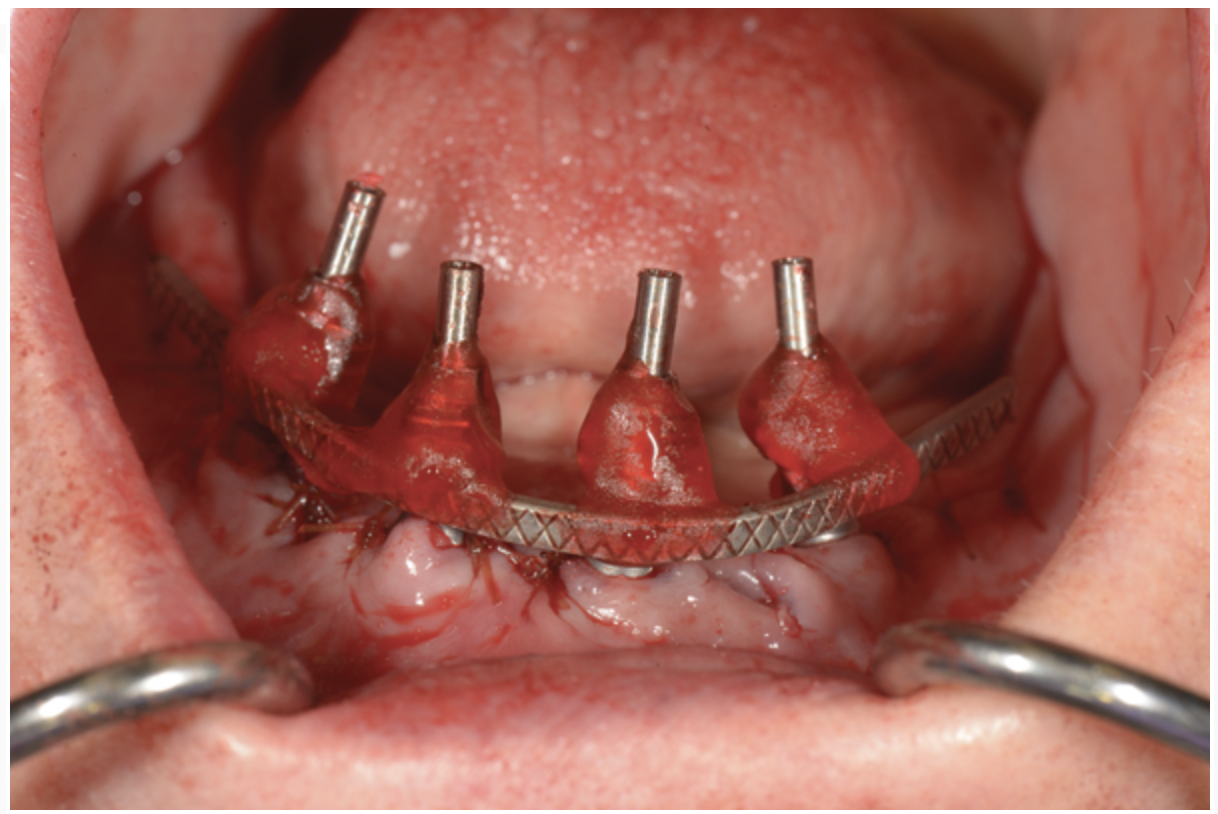

To start, a surgical impression is performed. Open-tray impression copings are secured to the restorative abutments, and a denture-strengthening bar is attached to the copings using a low-expansion pattern resin. The “salt and pepper” technique is used for precise control of the material, thereby avoiding contact with the surgery site and more effectively controlling working time. A plastic impression tray is modified in the occlusal areas where the impression copings will emerge and is tried-in to verify that there are no interferences. Polyvinylsiloxane impression putty is mixed and adapted over the impression copings and denture-strengthening bar. Impression material is also placed in the tray prior to seating. The impression coping screws are exposed and disengaged, allowing the impression to be easily removed. Rigid stabilization of the copings in the impression is verified (Figure 10 through Figure 12). The surgical index is performed using the same provisional prosthesis guide used during the surgery. Only the two anterior implants are indexed. The provisional prosthesis guide is seated to verify the absence of interferences with the two anterior temporary cylinders, and cold-cure acrylic material is applied through the access windows using a “salt and pepper” technique (Figure 13). The prosthesis is held in place with light pressure on the prosthesis guide over the palate or the posterior lingual mandibular ridge until the resin is cured. The VDO is verified after guiding the patient into occlusion with a bite registration recorded in the lab. Esthetic and functional parameters are verified, and the indexed prosthesis is removed with the attached temporary cylinders, and it is then disinfected in cold sterile solution.

Fig 10. Surgical impression—Open-tray impression copings are secured and splinted with a denture-strengthening bar using low-expansion pattern resin.

Figure 10